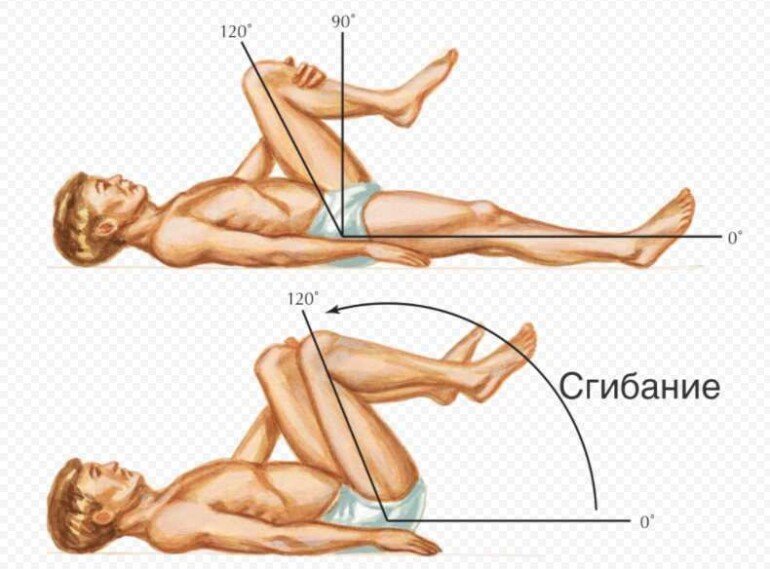

Диаграммы и схемы движения в суставах человека